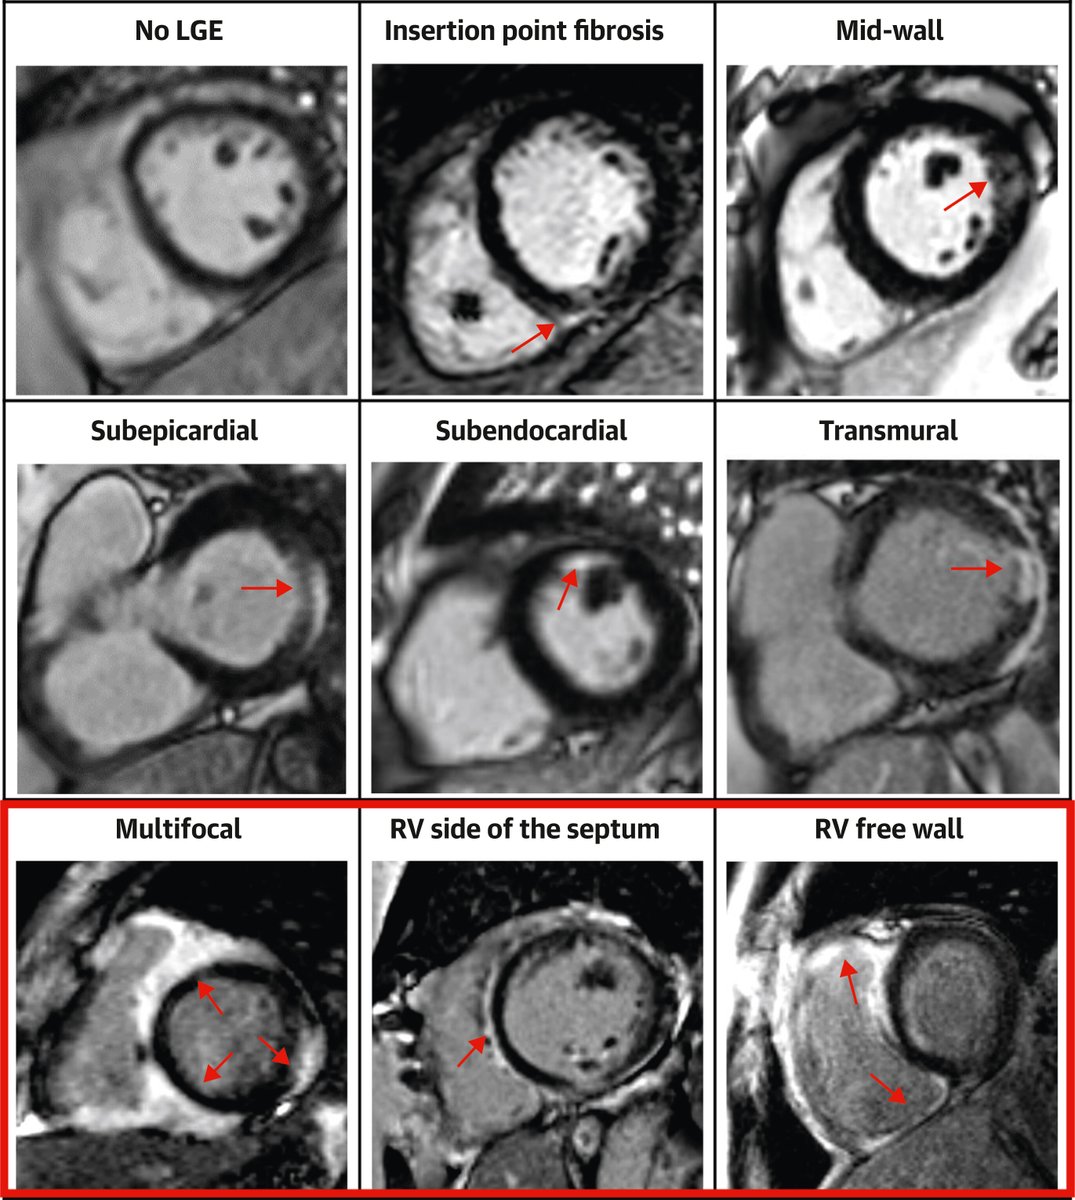

#WhyCMR by LGE in sarcoidosis, new precision in prognosis? Large #UK cohort of biopsy-proven cardiac sarcoidosis finds that LGE extent was an independent predictor of VAs or device therapy. #JACCIMG offers a novel approach to arrhythmic risk stratification https://t.co/PDK5fsXjMt